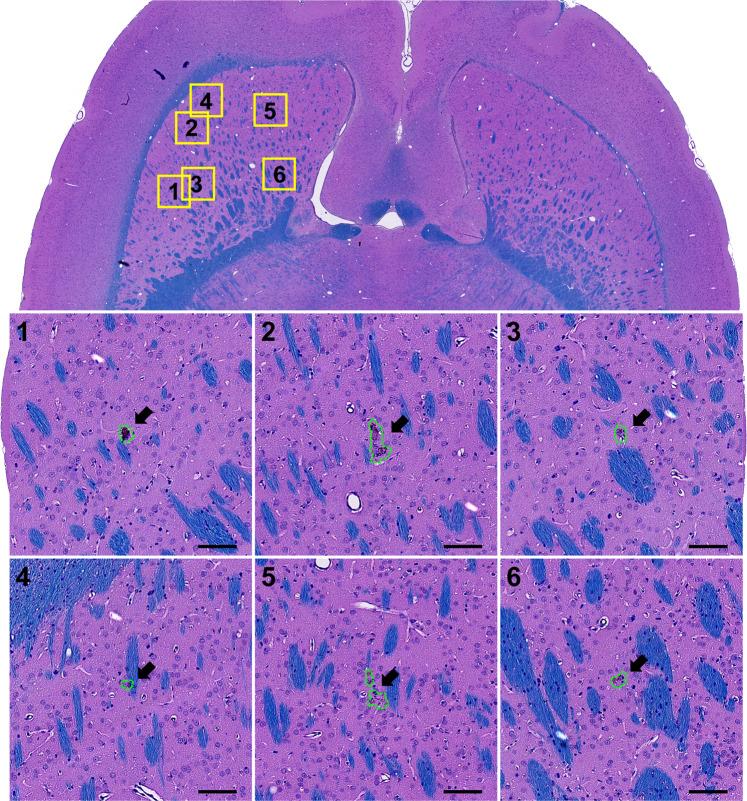

We investigated controlled blood-brain barrier (BBB) disruption using a low-frequency clinical transcranial MRI-guided focused ultrasound (TcMRgFUS) device and evaluated enhanced delivery of irinotecan chemotherapy to the brain and a rat glioma model. Animals received three weekly sessions of FUS, FUS and 10 mg/kg irinotecan, or irinotecan alone. In each session, four volumetric sonications targeted 36 locations in one hemisphere. With feedback control based on recordings of acoustic emissions, 98% of the sonication targets (1045/1071) reached a pre-defined level of acoustic emission, while the probability of wideband emission (a signature for inertial cavitation) was than 1%. BBB disruption, evaluated by mapping the R1 relaxation rate after administration of an MRI contrast agent, was significantly higher in the sonicated hemisphere (P < 0.01). Histological evaluation found minimal tissue effects. Irinotecan concentrations in the brain were significantly higher (P < 0.001) with BBB disruption, but SN-38 was only detected in <50% of the samples and only with an excessive irinotecan dose. Irinotecan with BBB disruption did not impede tumor growth or increase survival. Overall these results demonstrate safe and controlled BBB disruption with a low-frequency clinical TcMRgFUS device. While irinotecan delivery to the brain was not neurotoxic, it did not improve outcomes in the F98 glioma model.

我们使用低频临床经颅 MRI 引导聚焦超声(TcMRgFUS)设备研究了可控的血脑屏障(BBB)破坏,并评估了伊立替康化疗药物递送至大脑的效果和在大鼠脑胶质瘤模型中的效果。动物接受了每周三次的 FUS、FUS 和 10mg/kg 伊立替康或单独伊立替康治疗。在每次治疗中,四个容积式超声波靶向一个半球中的 36 个位置。通过基于声发射记录的反馈控制,98%的声发射目标(1045/1071)达到了预先定义的声发射水平,而宽带发射的概率(惯性空化的特征)大于 1%。通过给药 MRI 对比剂后测量 R1 弛豫率来评估 BBB 破坏,发现超声波治疗半球的 BBB 破坏明显更高(P<0.01)。组织学评估发现组织影响最小。BBB 破坏后,大脑中的伊立替康浓度显著升高(P<0.001),但仅在<50%的样本中检测到 SN-38,且仅在过量的伊立替康剂量下才检测到。伊立替康与 BBB 破坏并不会阻碍肿瘤生长或增加存活率。总的来说,这些结果表明低频临床 TcMRgFUS 设备可安全且可控地破坏 BBB。尽管伊立替康递送至大脑并未引起神经毒性,但它并未改善 F98 脑胶质瘤模型的结果。